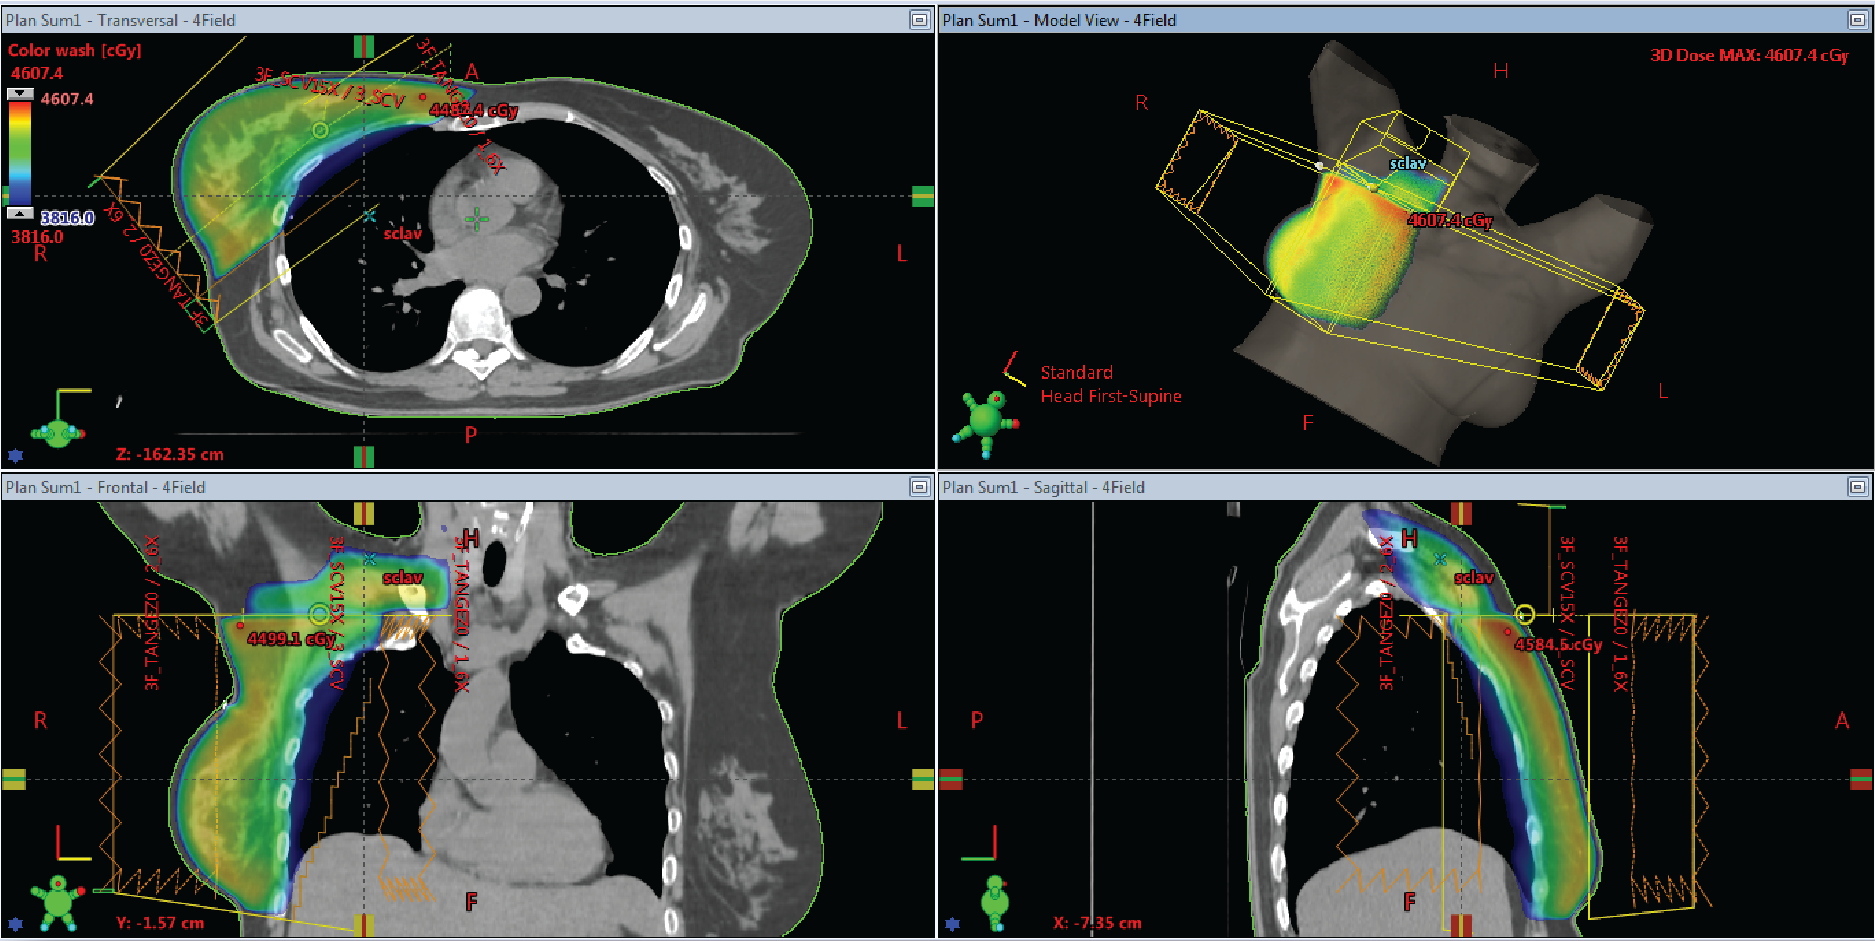

3 & 4 Field Breast Planning

EZFluence automatically sets the SCLAV and PAB field weighting. Control the match line in monoisocentric plans with EZFluence by increasing coverage and minimizing hot spots.